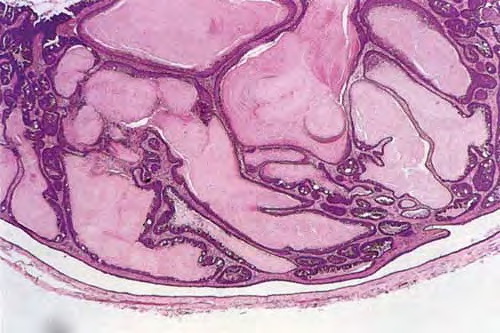

Hidradenoma papilliferum = الغدوم العرقي الحليمي